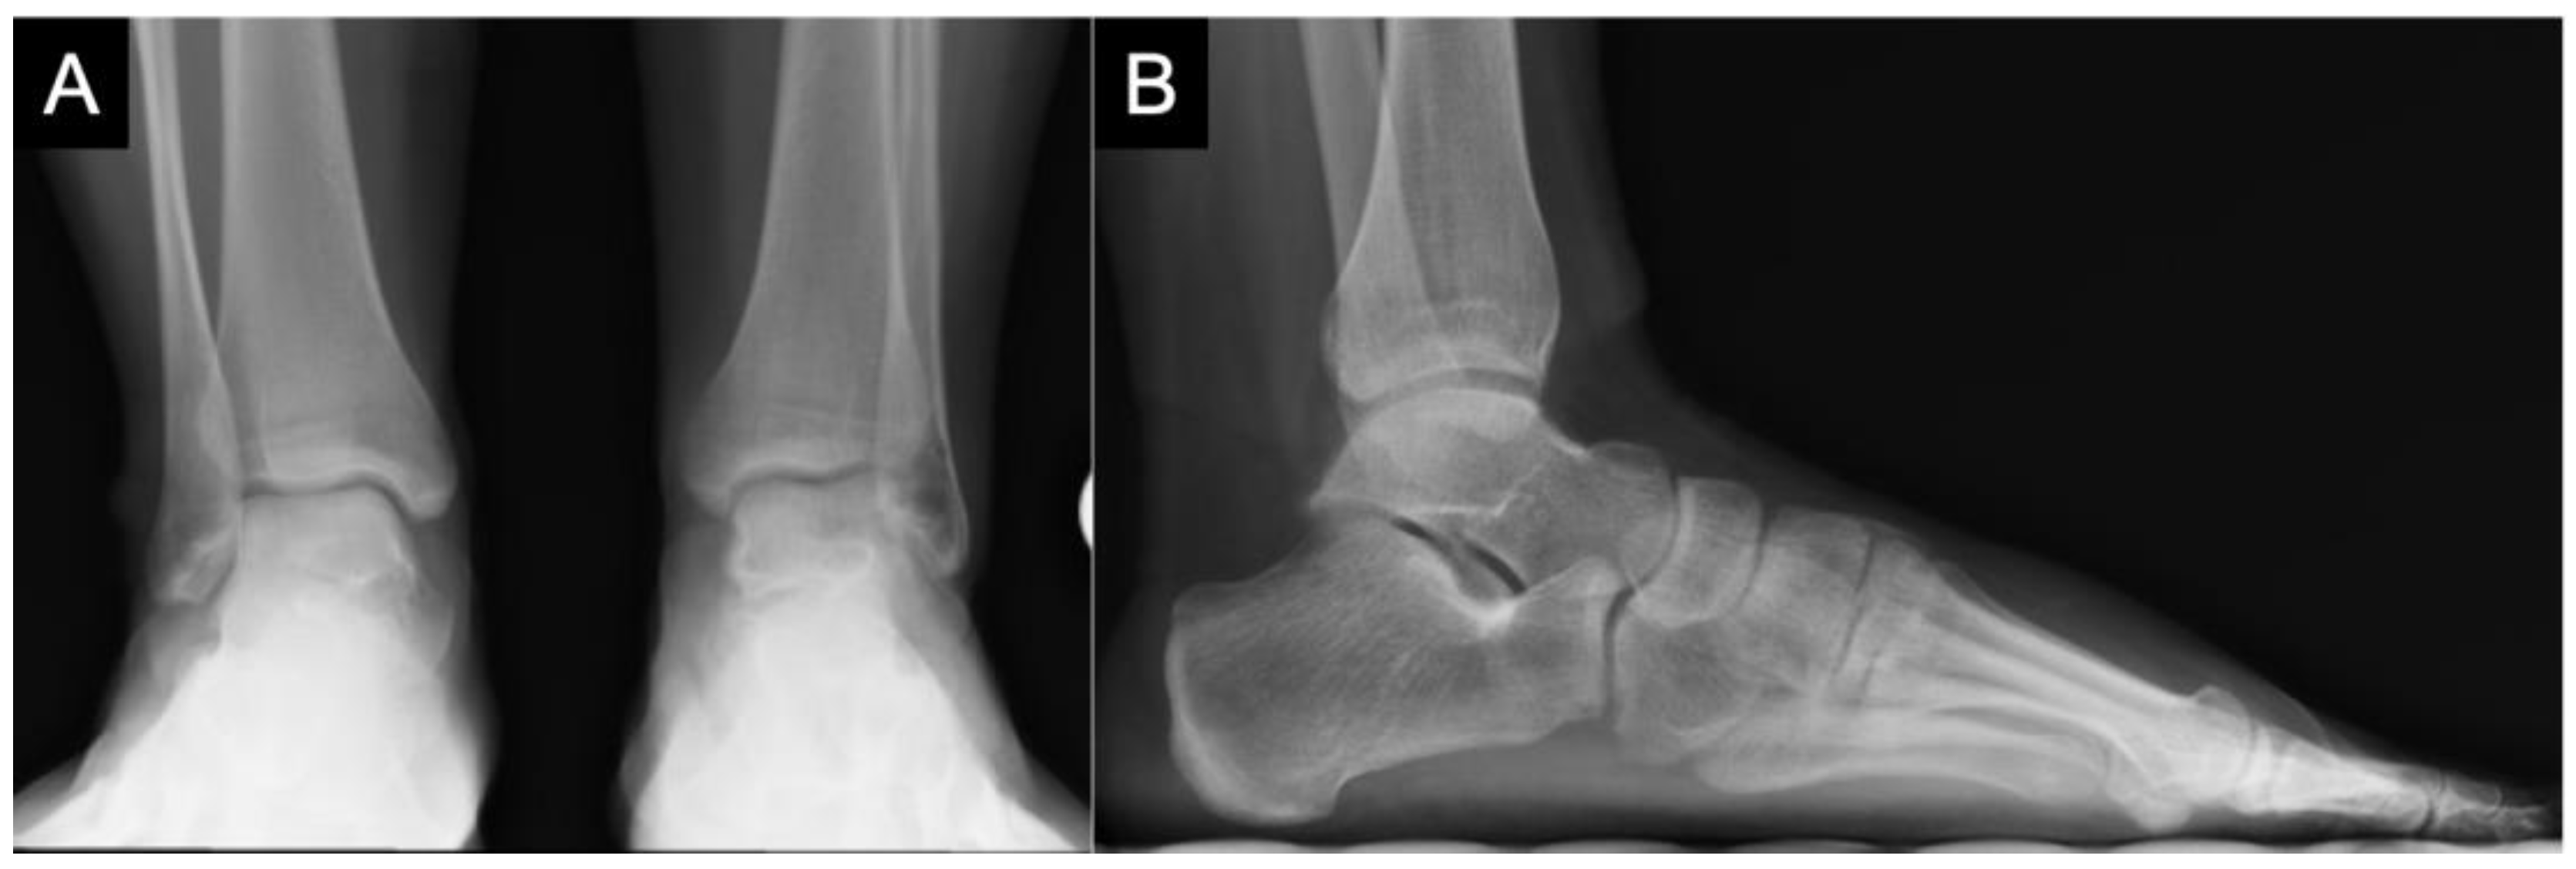

3. Diagnostics